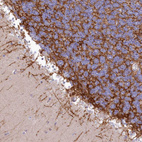

Immunohistochemical staining of human Cerebellum shows strong positivity in processes in cells in molecular layer.